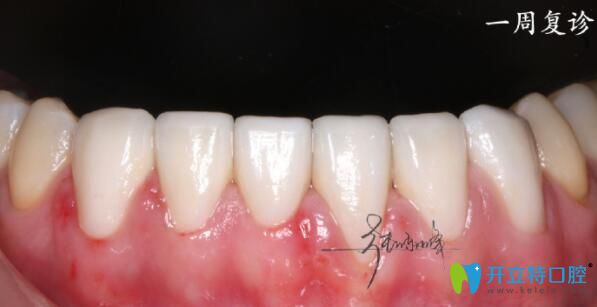

一周后復(fù)診拋光牙面,沒(méi)有任何問(wèn)題,就當(dāng)做自己的牙齒這位男士說(shuō):“以后再也不擔(dān)心張口了”。

牙齒貼面后